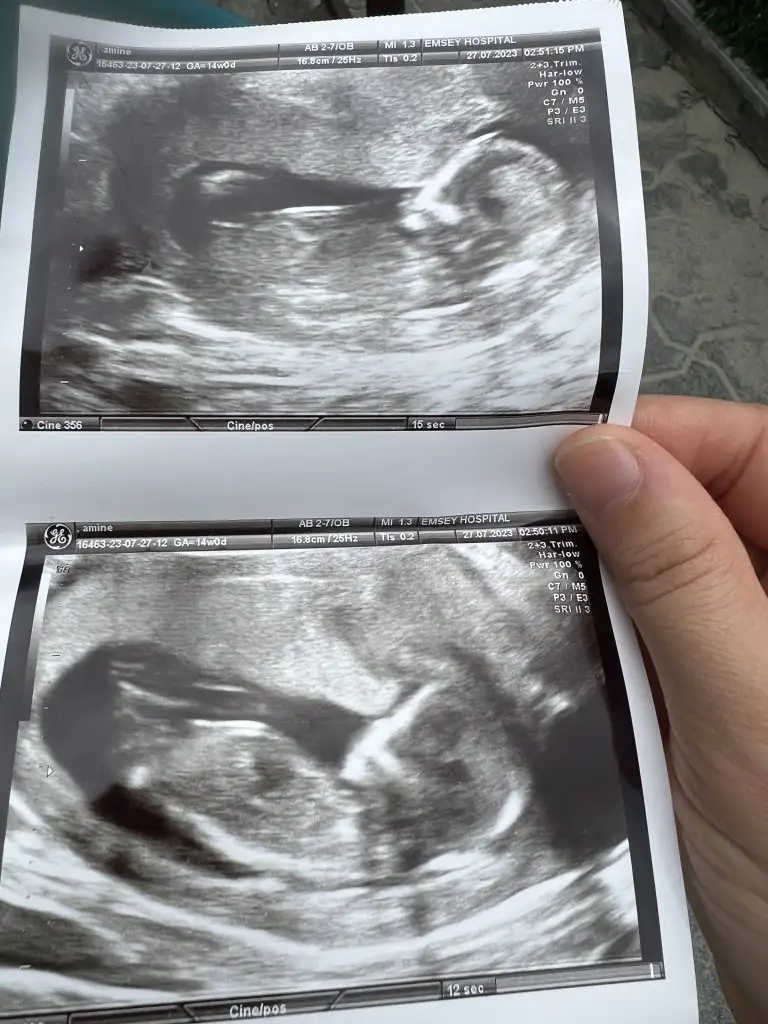

Hepsi karından çekim. Sizden yorum bekliyorum. 1 ay sonra net belli olacak inşallah. 6 haftalık ultrason, 11 haftalık ultrason ve 14 haftalık var. 16 da kendini göstermedi bacakları kapalıydı. Ayrıntılı ultrasonda belli olur artık dedi doktorum. Sizlerin de tahminini bekliyorum.